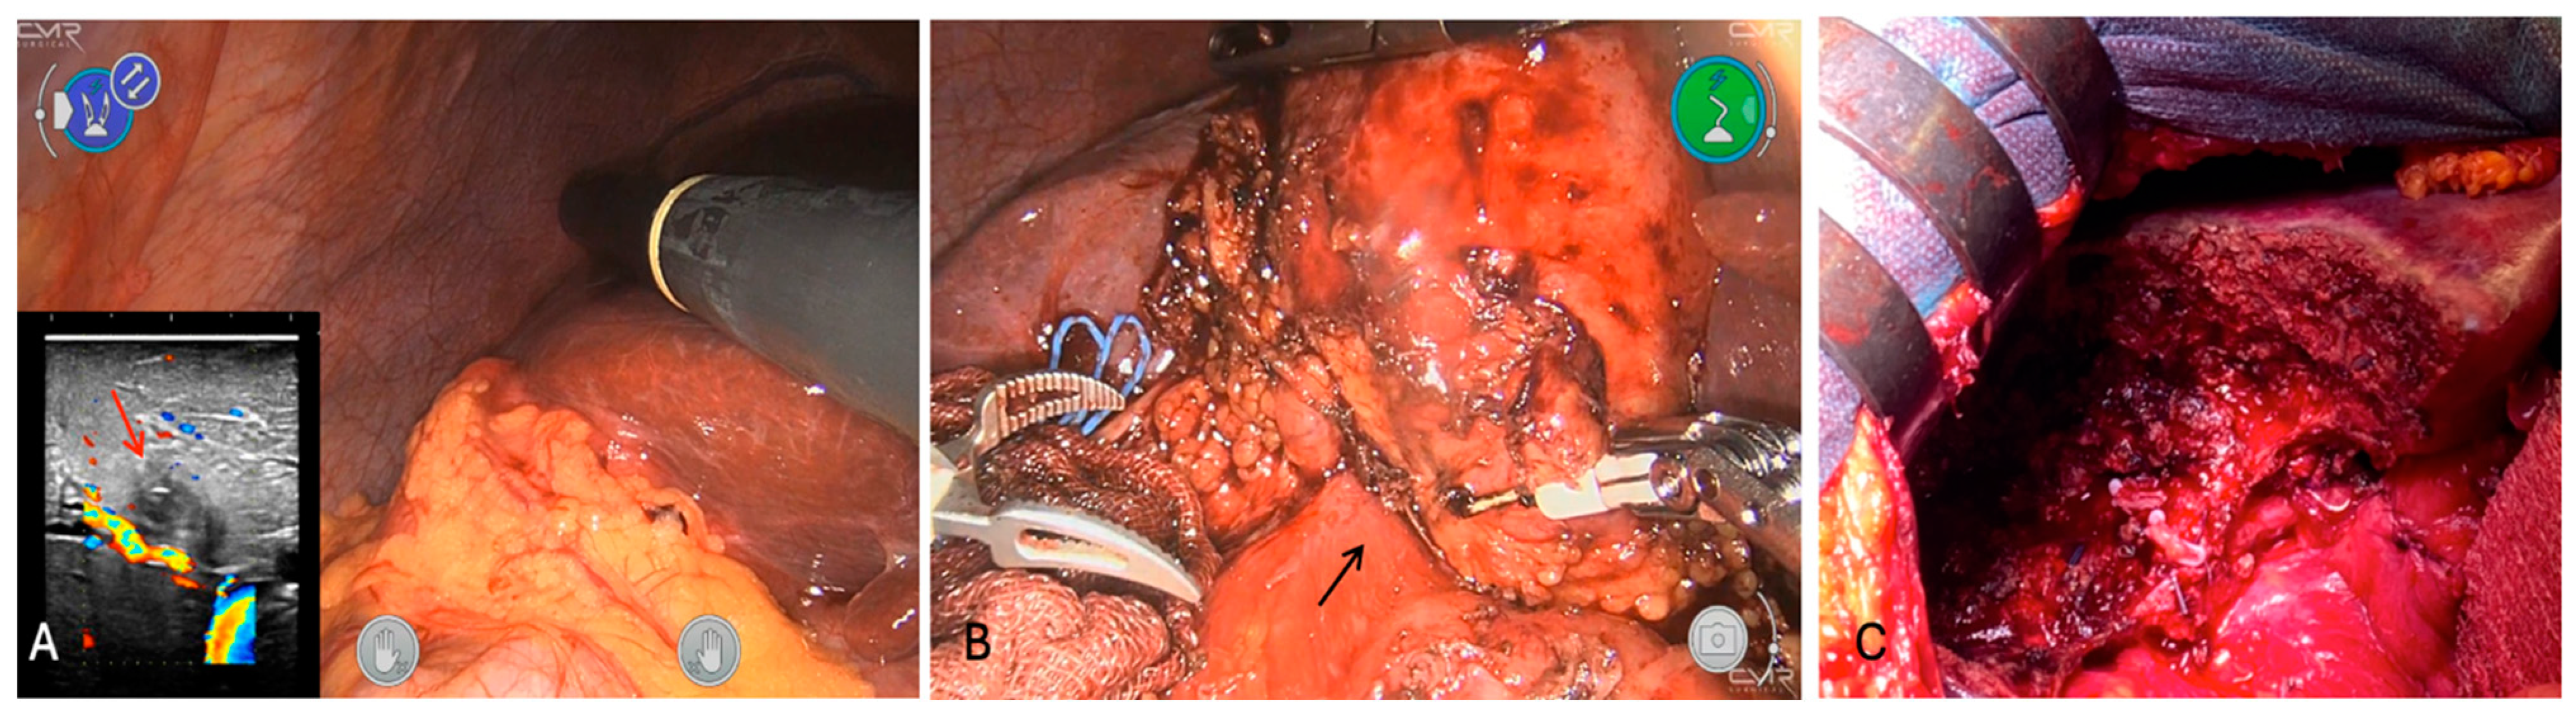

According to the biopsy, the patient was scheduled for robot-assisted cholecystectomy (CMR Versius Surgical Robotic System, Versius®). Still, intraoperatively, a highly suspicious feature of an ICC tumor infiltrating the gallbladder was revealed without any clear dissection plane with the duodenum (Figure 7); thus, after proper informed consent, a non-anatomic open S4b-S5 resection en bloc with the gallbladder and marginal duodenal resection, plus lymphadenectomy, was performed.

Figure 7.

Intraoperative findings. (A) Hypoechoic nodule with a faint hyper rim in segment 5 next to P5-8 (red arrow); (B) no dissection plane between gallbladder and duodenum (black arrow); (C) final cut surface after S4b-S5 and partial excision of duodenum.

The post-operative course was uneventful and histologically the tumor was characterized by a heavy inflammatory infiltrate consisting of plasma cells and lymphocytes with no evidence of malignancy. The final pathology report revealed an inflammatory pseudotumor (IPT) of the liver (Figure 8).